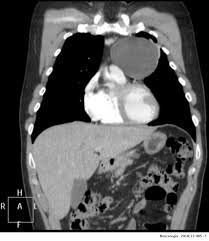

Thymic cyst

A thymic cyst is a benign mediastinal disease which has been reported to be the second most common type of primary mediastinal cyst. Thymic cysts are rare, and the majority are believed to be congenital in origin.